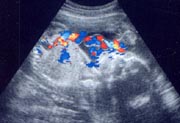

男の子、女の子、それぞれの外性器は完成していて、超音波検査でほぼ正確に性別判定ができるようになります。体の中では内性器(男の子は精巣、女の子は卵巣)ができて、それぞれにホルモンを分泌しはじめます。